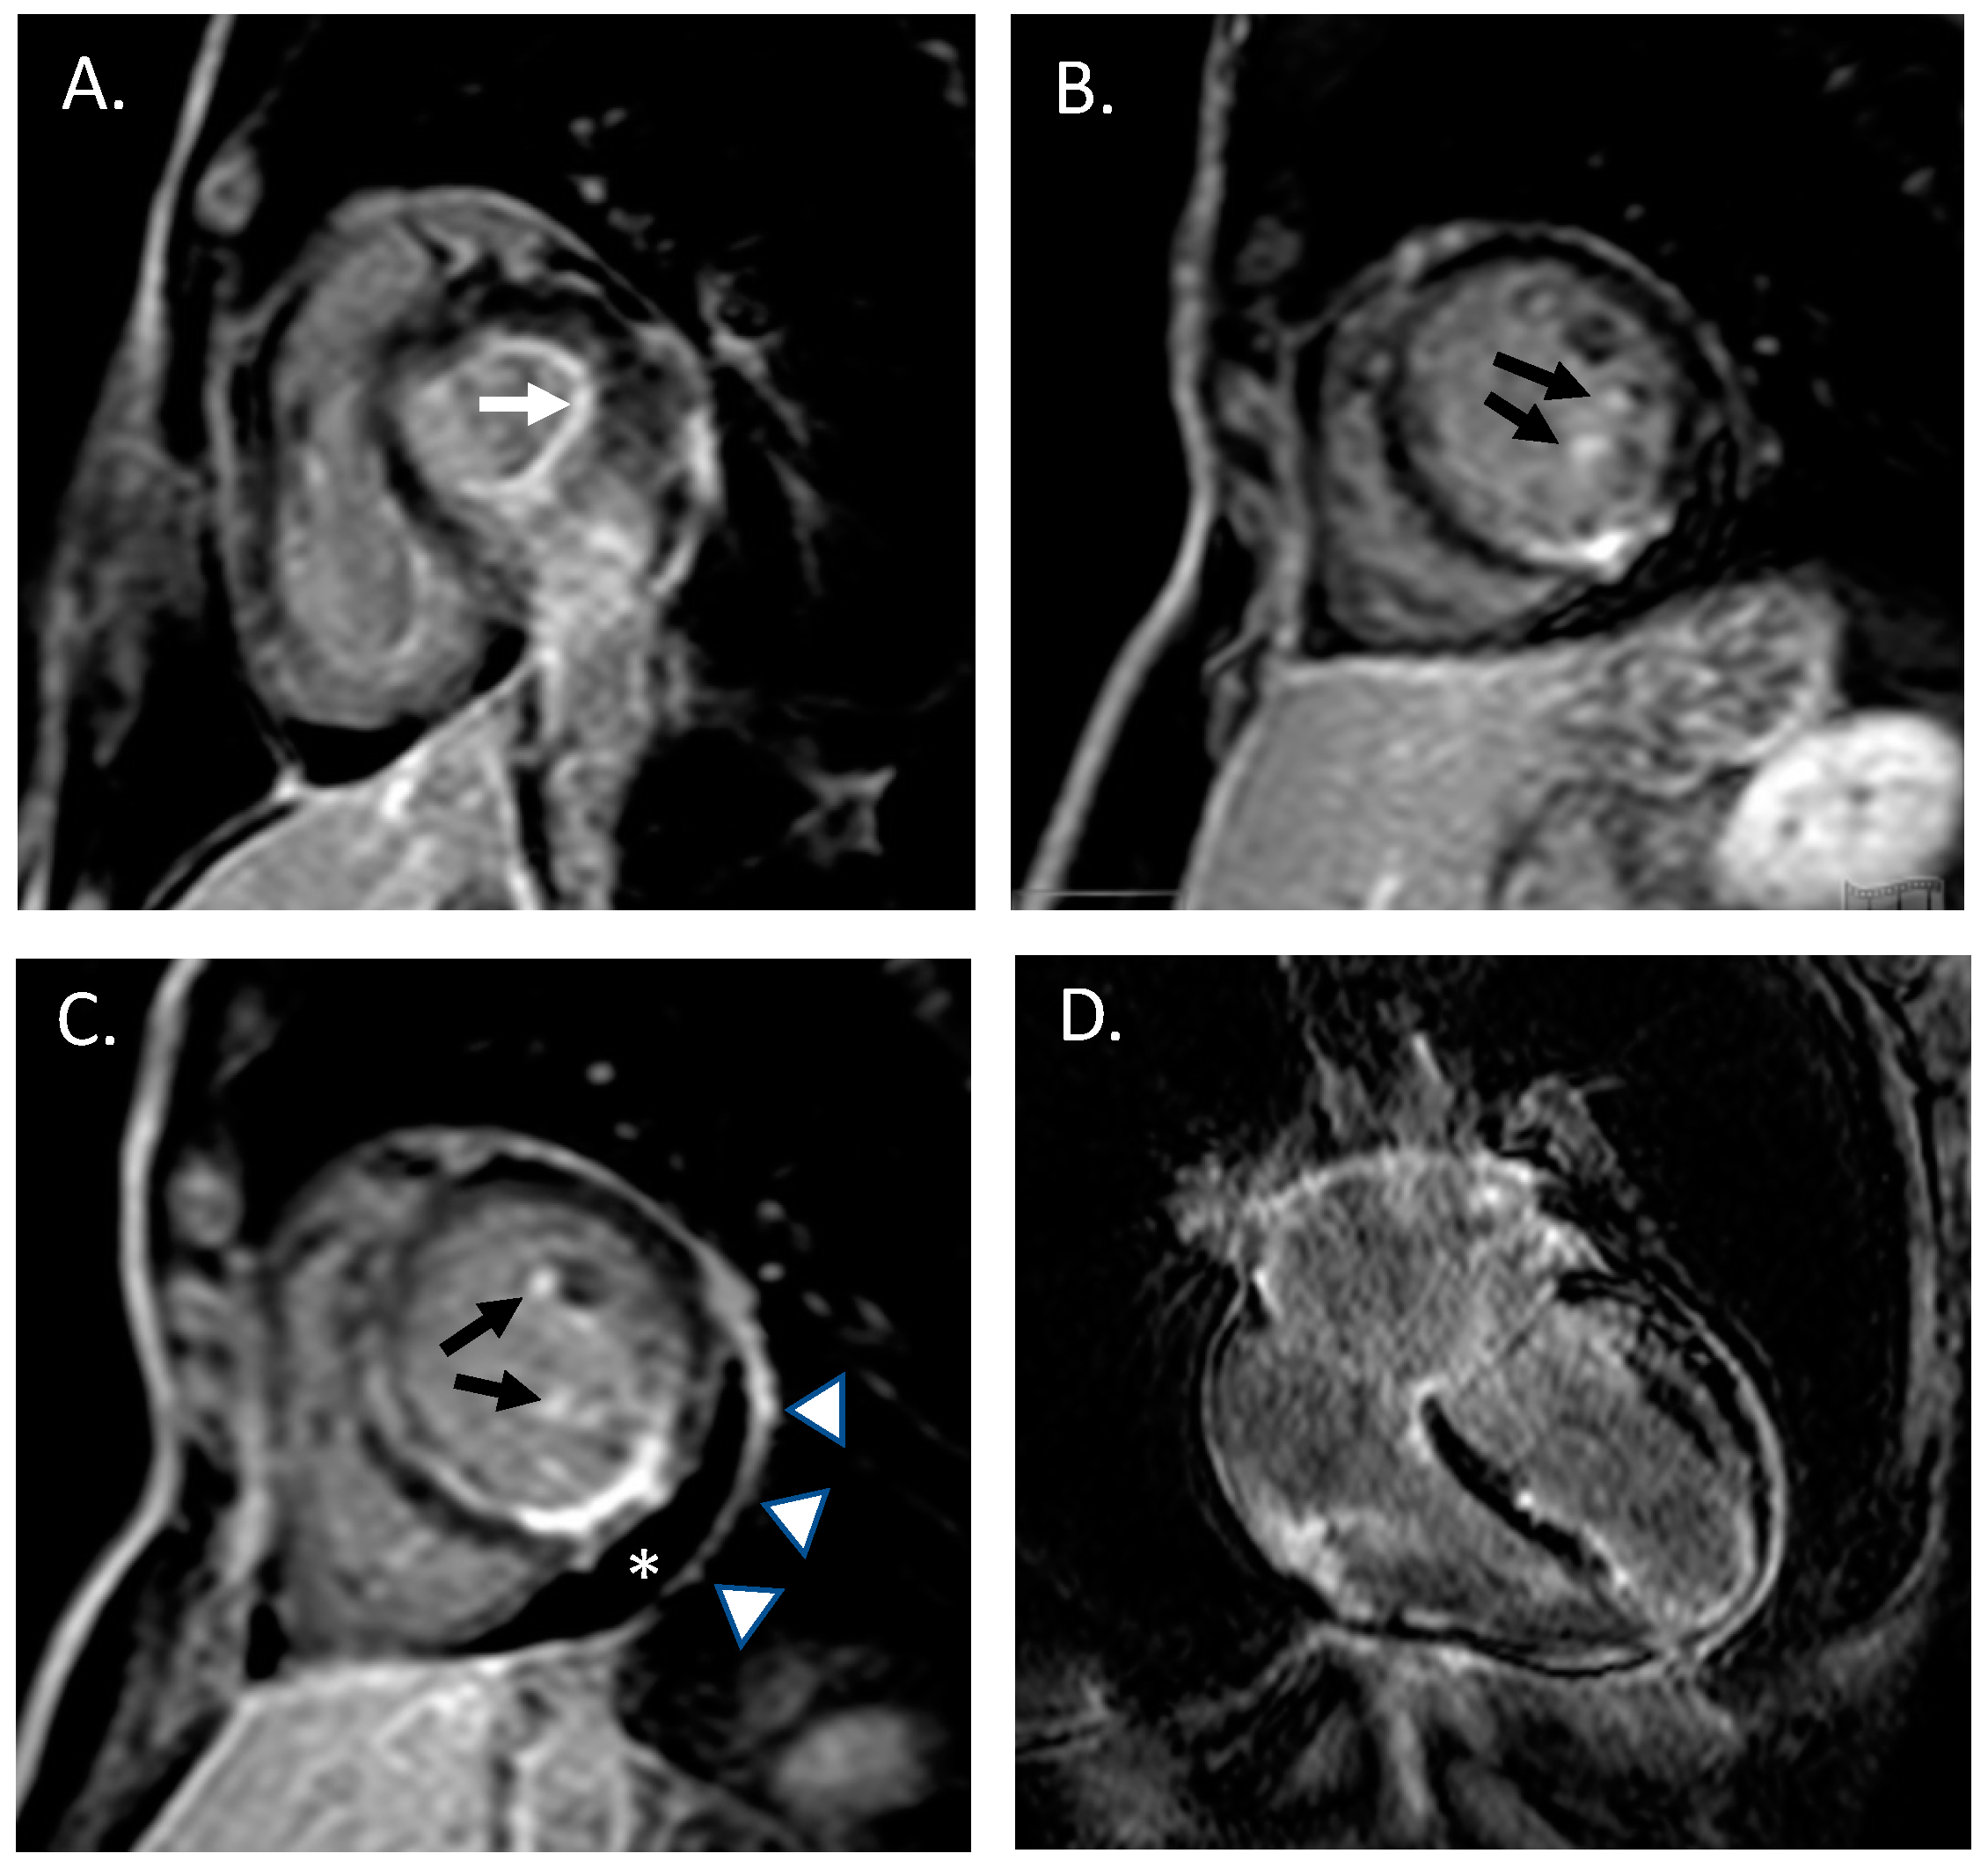

She had a medical history of severe asthma with forced expiratory volume in the 1st second (FEV1) < 50% of the predicted value and three years before she underwent surgery for nasal polyposis. She denied any cardiovascular risk factors, as well as smoking, alcohol assumption or any illicit drug injection. Three months before, she received the second dose of the BNT121b1 mRNA SARS-CoV2 vaccine. The patient did not report any history of fever, night sweats, unintentional weight loss, dyspnea, gastrointestinal symptoms, joint pain, myalgia or cutaneous manifestations. She reported intermittent use of non-steroidal anti-inflammatory drugs (NSAIDs) for recurrent episodes of headache. Laboratory tests, performed at Emergency department, showed a mild increase of high sensitivity cardiac troponin (hs-TnI 48 ng/L, 99th percentile upper reference limit 14 ng/L) and increased eosinophil count (2080/mm3, 19.5%, total blood cell count 10.68 × 103/microL). Serum creatinine, thyroid enzymes, electrolytes, and serum transaminases were within the reference ranges. C-reactive protein, platelet count and ferritin were increased (respectively: 8 mg/dL, 300 × 103/microL and 420 micrograms/L). A coronary angiography was then performed showing normal coronary anatomy without significant coronary atherosclerosis. In the suspicion of myopericarditis, cardiac magnetic resonance (CMR) with a contrast medium was performed. Overall, late-gadolinium enhancement images were suggestive of an active inflammatory process simultaneously affecting the endocardium (with a prominent involvement of the left ventricular papillary muscles and mitral leaflets), the myocardium of the left and right ventricles and the left and right atria, and the pericardial layers [17] (the so-called “pancarditis”; Figure 1).

Figure 1. Cardiac MRI acquisitions obtained late after contrast injection, showing multiple areas of late gadolinium enhancement (LGE, “bright signal”) simultaneously affecting the endocardium, the myocardium and the pericardium. (A) short-axis view images documenting LGE involvement of mitral valve anulus (white arrow) and (B,C) left ventricular papillary muscles; (C) short-axis mid papillary view showing mild pericardial effusion (asterix) and pericardial enhancement; (D) four-chamber view image showing diffuse myocardial LGE involving left and right ventricles and both atria.